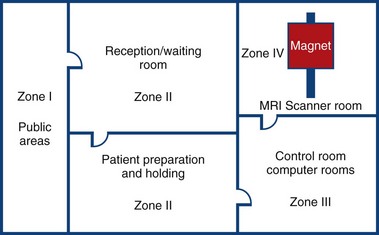

MRI Zone 4

Zone 4: Magnet Room

Authorised access only

The scan room door is always locked when unattended

Metal is removed

Danger signs

When the scan room door is opened, the MRI Safety barrier must be implemented at all times by MRI personnel

Forms for safety and consent

MRI Zone 3

Zone 3: Control Room

All metal removed

Locks on doors

Caution signs

Authorised access only

MRI Zone 2

Zone 2: Patient Screening and Prep

Patients and families undergo screening and are cleared to enter the magnetic area

MRI Zone 1

Zone 1: Unrestricted area (public walkway)